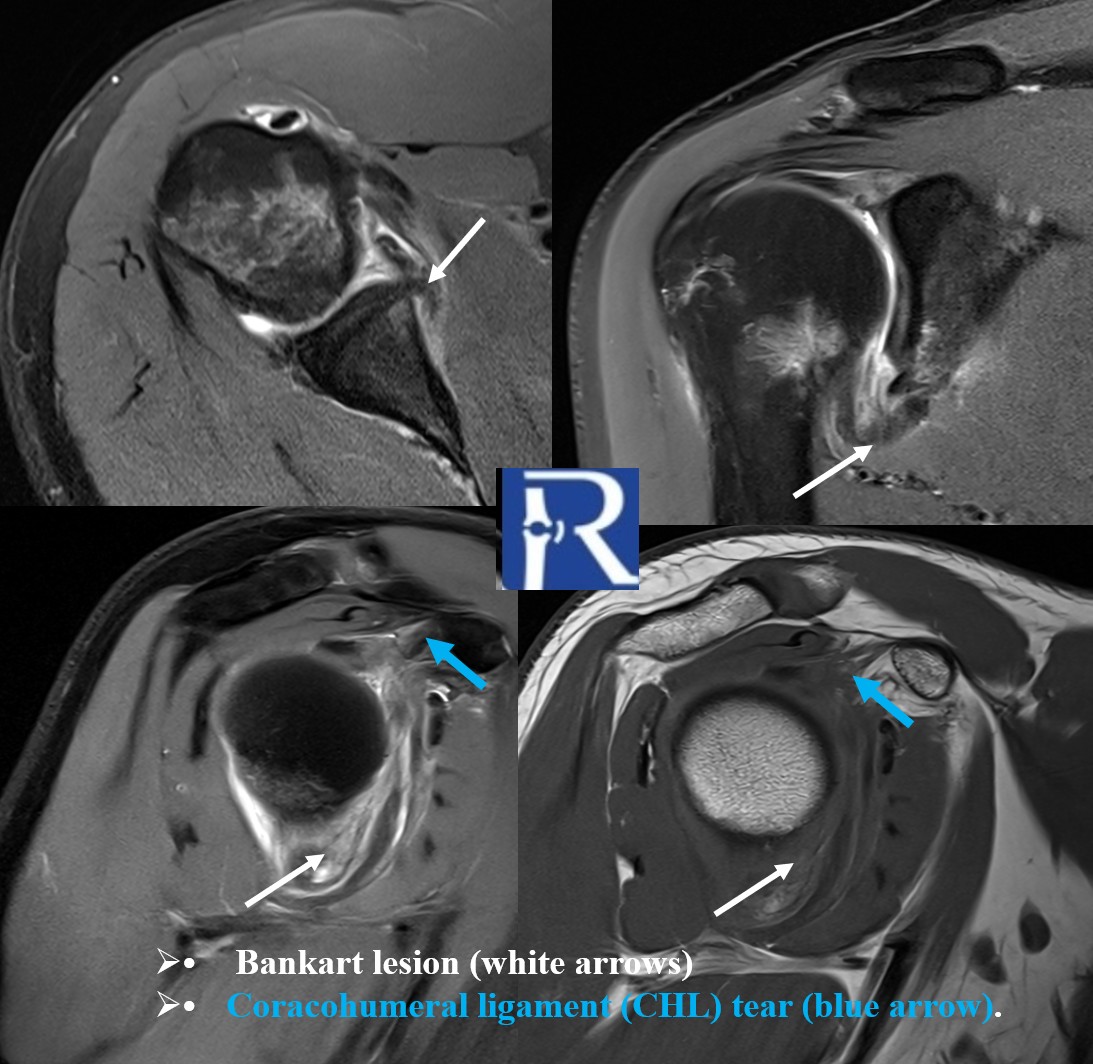

Clinical Presentation A 29-year-old male presented with recurrent anterior shoulder dislocation. The patient reported multiple episodes of instabil ...